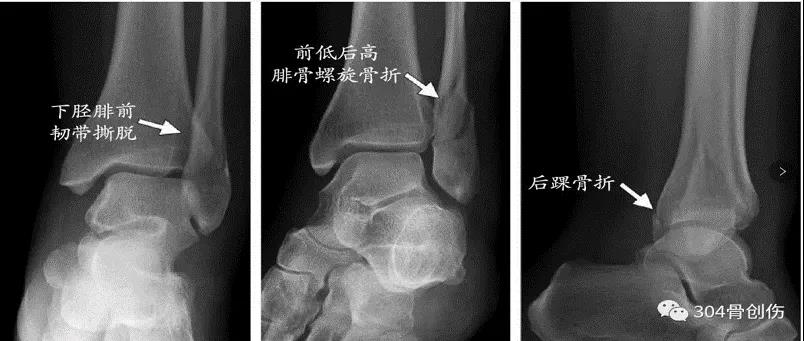

Lauge-Hansen-旋后外旋(SE)损伤时足呈跖屈内收内翻位,距骨外旋(胫骨内旋)。Ⅰ°:距骨外旋使腓骨受到向外、向后的应力,下胫腓前韧带损伤或韧带附着点撕脱性骨折,或者同时又骨间韧带损伤。Ⅱ°:外力继续作用,腓骨继续受到向外、向后的旋转应力,造成腓骨的螺旋性骨折。(特点:腓骨骨折线从后上向前下。并且多位于下胫腓联合部位。)Ⅲ°:外力继续作用,下胫腓联合后韧带紧张,造成下联合后韧带的断裂或后踝的撕脱骨折。Ⅳ:外力还继续,距骨旋转使三角韧带紧张,造成内踝的撕脱性骨折或者是三角韧带的断裂